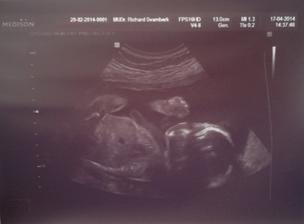

Jáchymek - -9. až 0. měsíc 🙂 - 2. těhotenství

24. srpna 2014 - 39+2tt - ve 4:24 hod. s mírami 49 cm a 2,97 kg se nám po náročném (pupečník kolem krku), ale zato rychlém porodu narodil náš druhý poklad. Šimonek mu vybral jméno Jáchym, my s tatínkem doplnili druhé jméno Pavel - JÁCHYM PAVEL KOLAŘÍK.